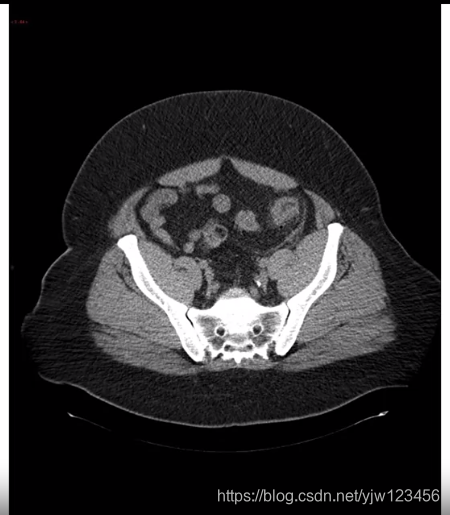

那3维数据是怎样的呢,假设接受CT扫描,它可以得到你身体的三维模型的X光扫描。

可以得到人体躯干的不同切面

所以3维数据通常除了高度和宽度外还有一个深度:

注意3维图像中还是会有一个通道数的,这里假设是黑白图片,所以通道数为1。